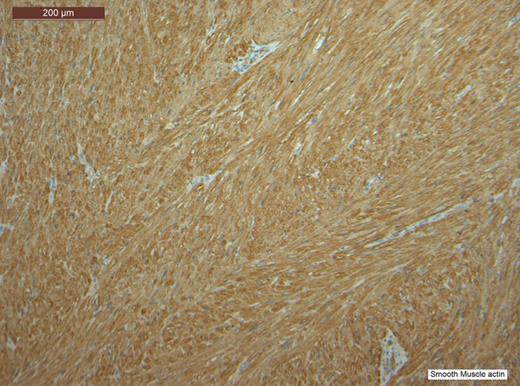

Histopathological analysis of the lesion, including immunohistochemical profiling, revealed a well-circumscribed nodular tumour composed of smooth muscle cells with eosinophilic cytoplasm and spindle-shaped nuclei. The cells were arranged in interlacing fascicles with evidence of perinuclear vacuoles using haematoxylin and eosin staining. There was no evidence of necrosis, mitosis or significant nuclear pleomorphism. The specimen was negative for CD117 staining, hence excluding the possibility of a gastrointestinal stromal tumour. It was also negative for S100. However, stain was positive for smooth muscle actin (SMA) and desmin, which confirmed that specimen was of muscular origin. The histology therefore identified the lesion as a leiomyoma (Figs 2–6).